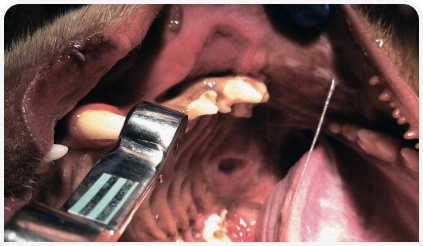

Сосудистые заболевания кожи

Сосуды кожи играют ключевую роль в работе множества гомеостатических механизмов, поэтому их поражение приводит к весьма тяжелым последствиям. Элизабет Гудейл анализирует возможные причины.

Чаще всего поражаются сосуды в участках кожи над точками давления и в дистальных отделах конечностей, таких как подушечки лап, хвост, ушные раковины и мошонка.

Истинный васкулит часто вызывает некроз и изъязвление эпидермиса, что нередко сопровождается системными клиническими проявлениями.

Ишемическая дерматопатия, или васкулит с небольшим содержанием клеток, как правило, вызывает ишемические поражения эпидермиса, например, алопецию и изменения содержания коллагена.

Чаще всего поражаются сосуды в участках кожи над точками давления и в дистальных отделах конечностей, таких как подушечки лап, хвост, ушные раковины и мошонка. Васкулит часто вызывает развитие тяжелого клинического синдрома с системными проявлениями, образованием язв и некроза кожи, в то время как ишемическая дерматопатия, как правило, протекает намного легче, а повреждения связаны с гипоксией эпидермиса. Во всех случаях должны быть по возможности идентифицированы фоновые триггеры и, хотя дерматопатии и ишемические дерматопатии лечат аналогичными препаратами, терапию всегда подбирают согласно степени тяжести заболевания.